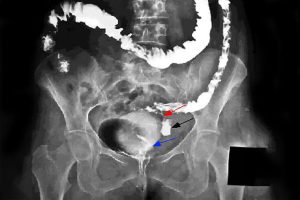

Early Diagnosis

Investing in new technologies and AI to detect bowel cancer earlier, when it is most treatable and survivable.